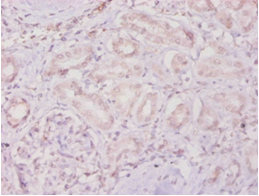

Immunohistochemistry of paraffin-embedded human kidney tissue using CSB-PA07419A0Rb at dilution of 1:100